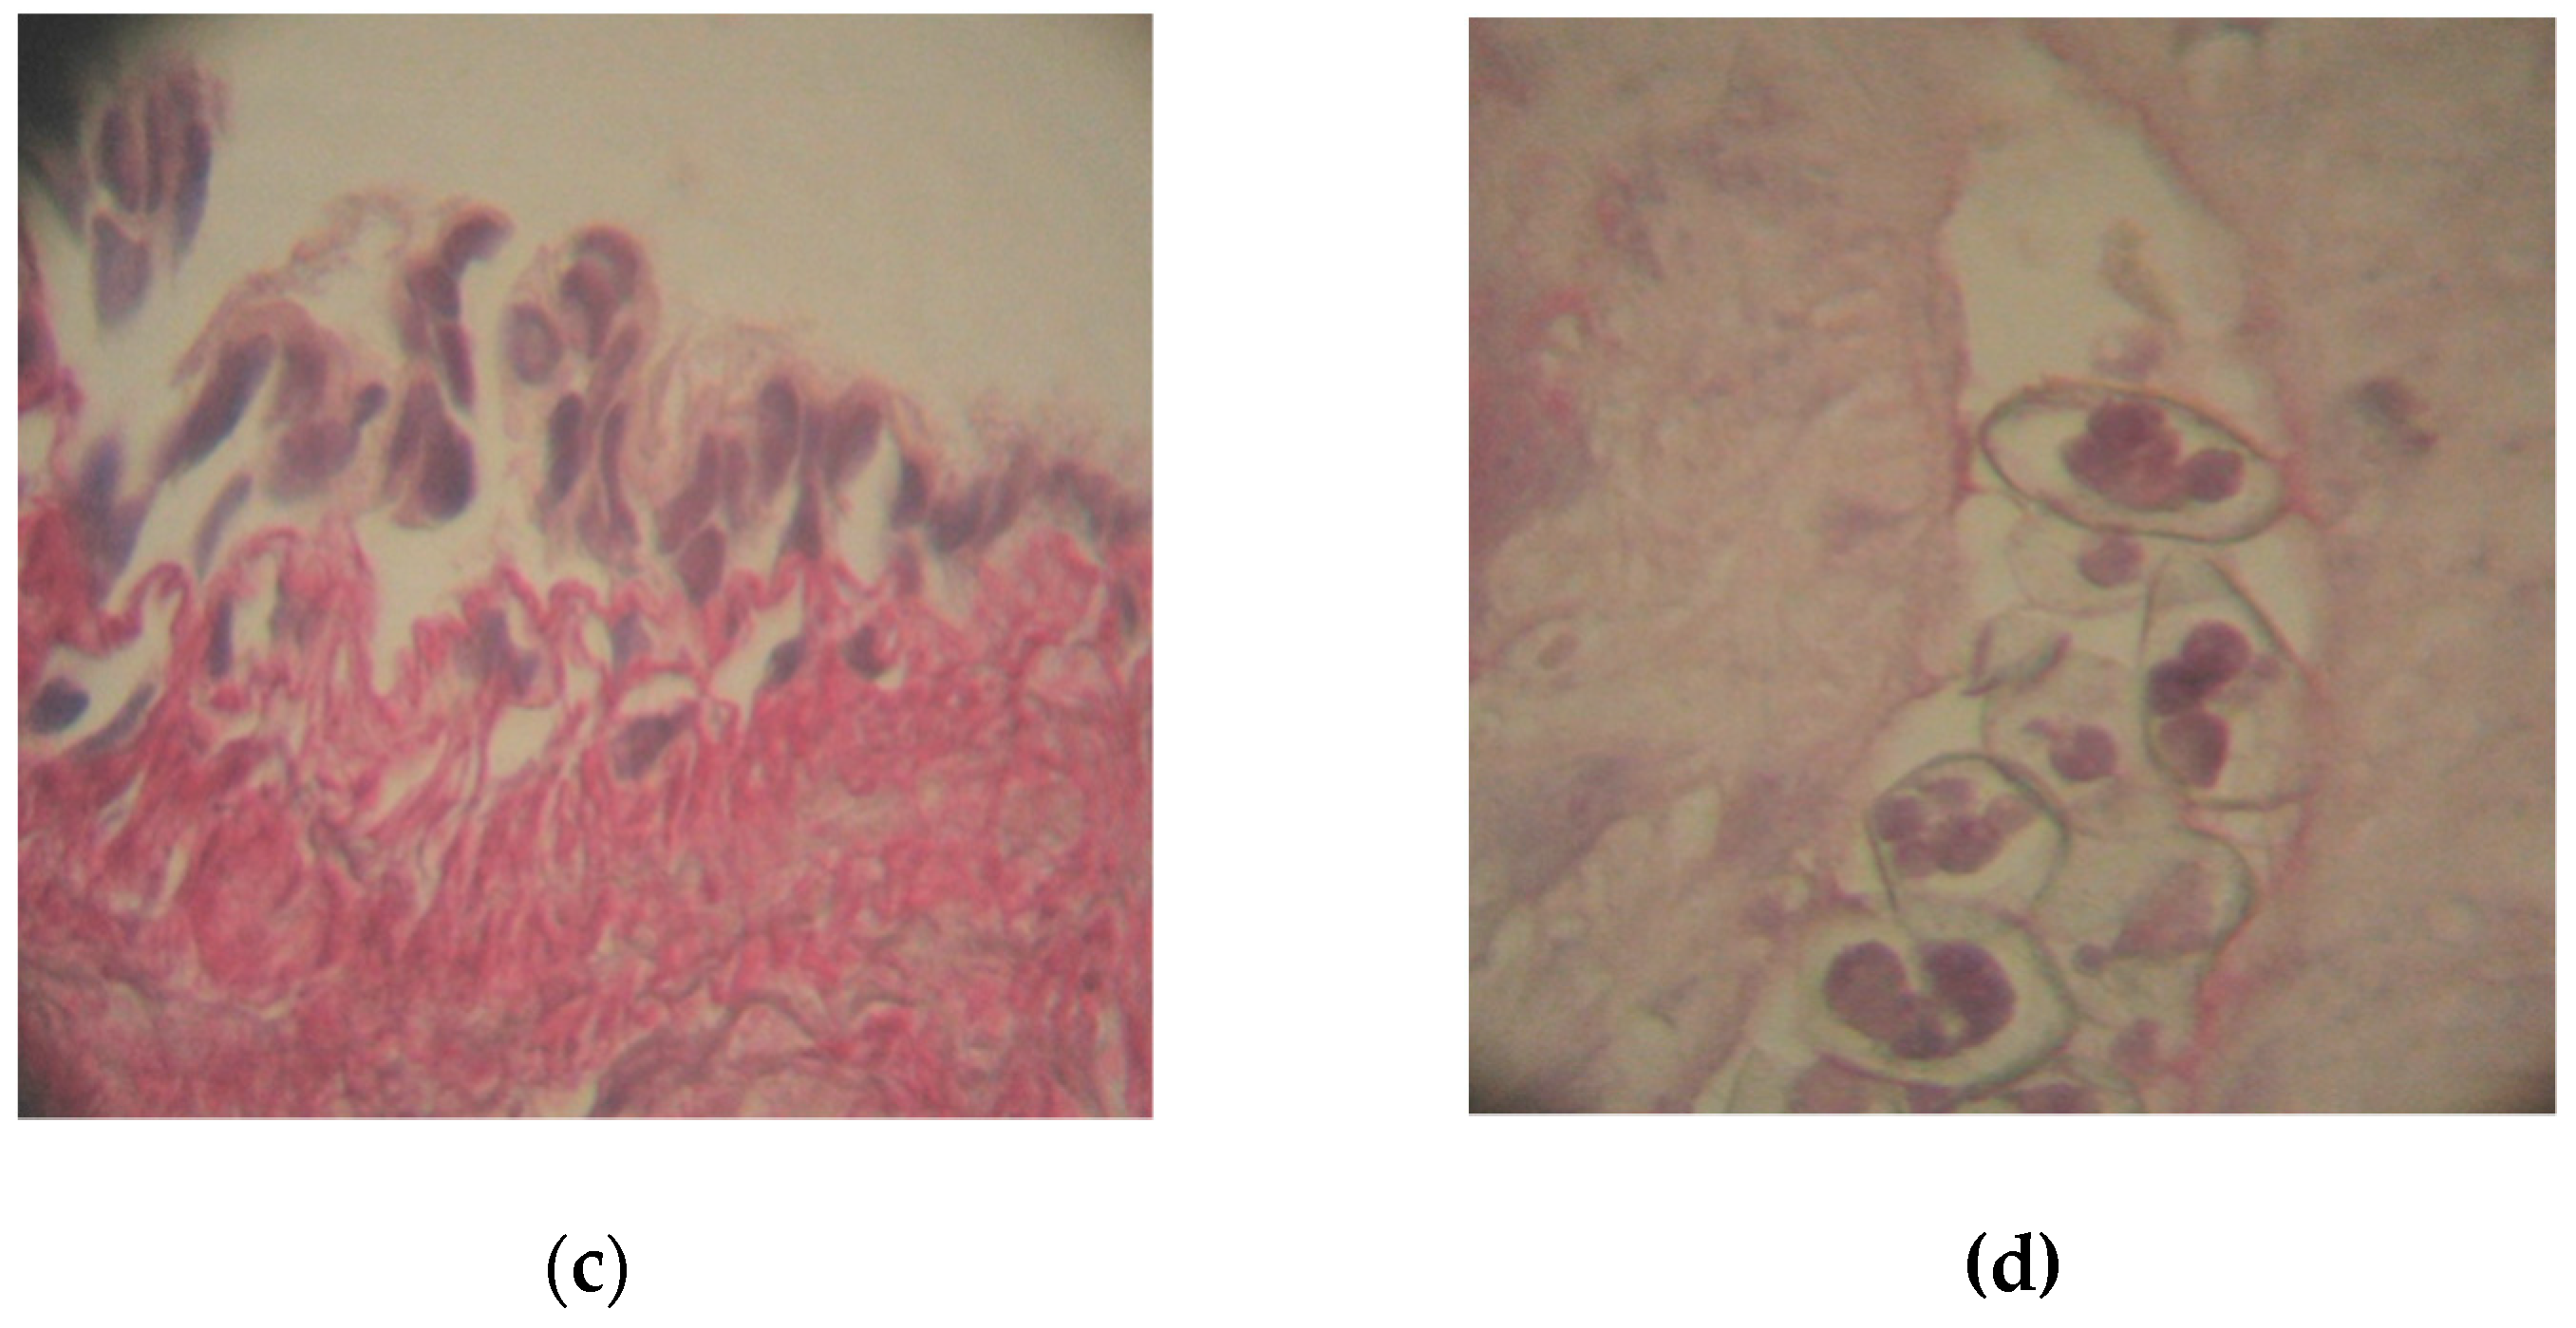

3.4. The Action of Actara 25 WG Insecticide on the Lung in Pelophylax ridibundus